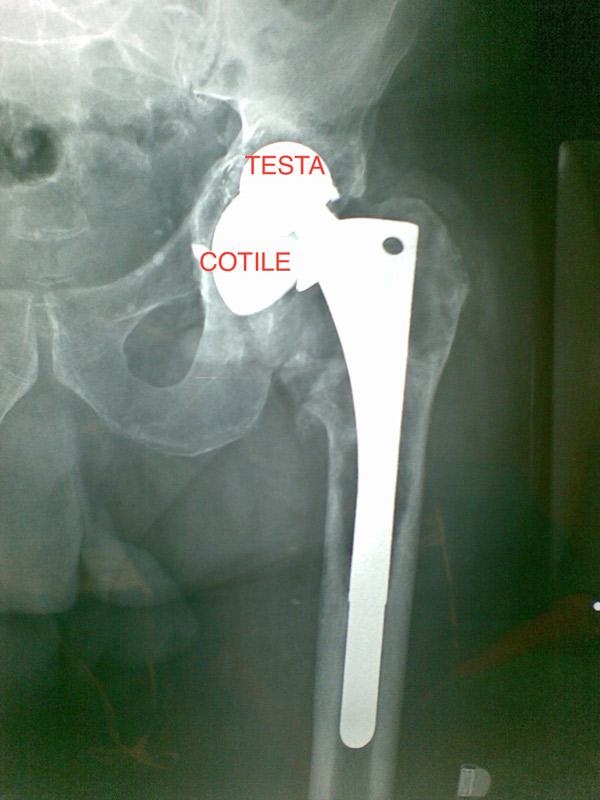

Caso clinico di paziente improvvisamente impossibilitato a deambulare per grave sintomatologia dolorosa e accorciamento dell’arto sinistro. Portatore di protesi d’anca sinistra impiantata 20 anni prima e mai controllata.

Fig. 1 Radiografia: dislocazione superiore della testa protesica femorale